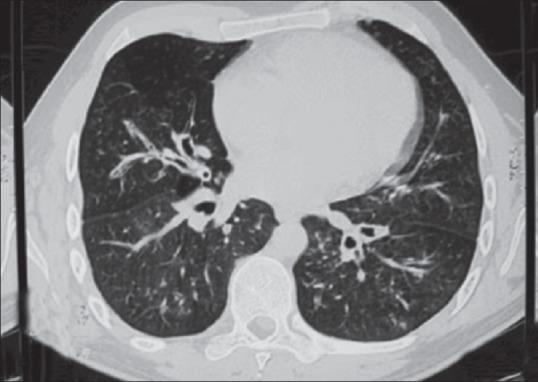

Cutaneous leucocytoclastic vasculitis and pulmonary tuberculosis: an uncommon association.